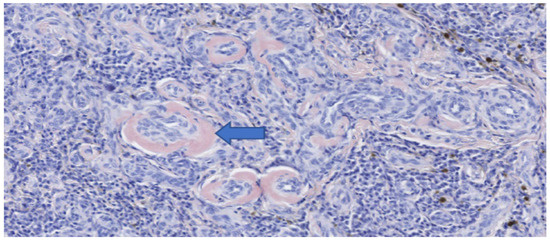

Figure 9.

Immunohistochemistry of the esophageal mass after surgical excision (MUM-1 stain). High power view of positive plasma cells and intralesional amyloid deposits.

The mass measured approximately 7 cm in length (Figure 6). Histopathological and immunohistochemical examination of the mass revealed that despite the abundant necrosis and hemorrhage, there was a neoplastic proliferation of plasma cells with extracellular amorphous eosinophilic material interpreted as amyloid based on Congo red staining (Figure 7 and Figure 8). Therefore, a diagnosis of a plasma cell tumor with perivascular amyloid deposition was made. This diagnosis was confirmed by immunohistochemistry (IHC) with a monoclonal anti-multiple myeloma oncogene 1 (MUM-1) antibody (clone MUM1p, Catalog #GA64461-2, Dako Omnis, Agilent, Richmond, VI, USA) (Figure 9).